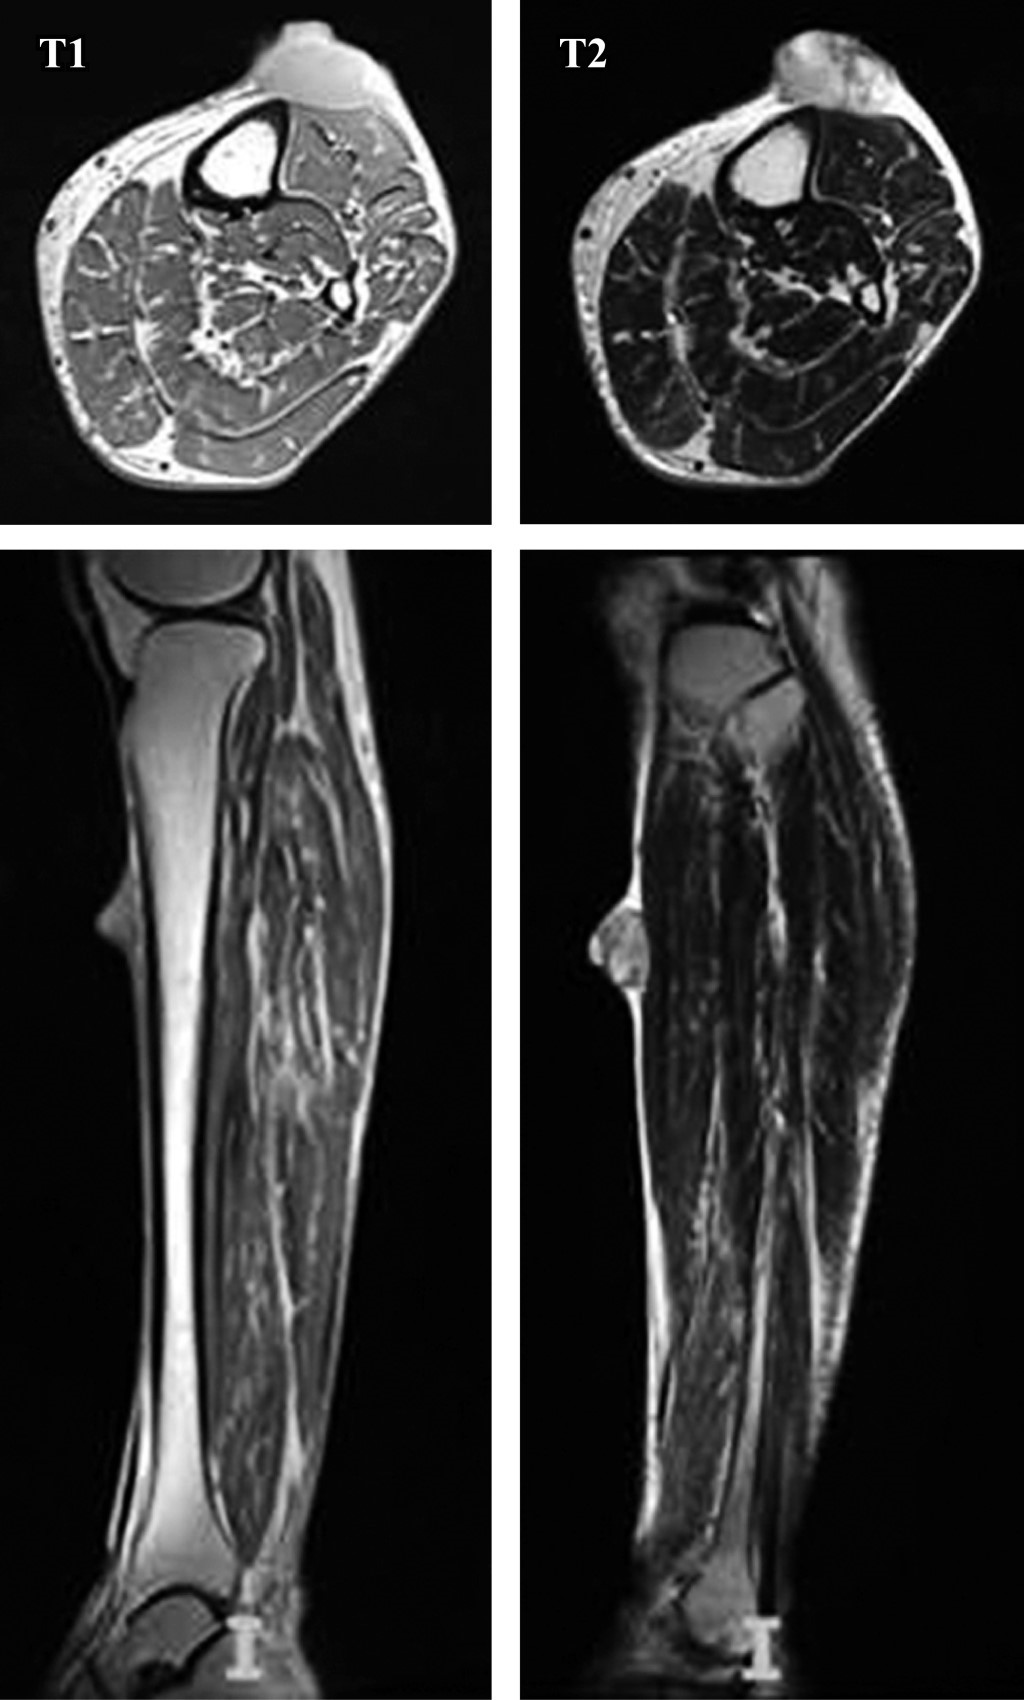

Las radiografías simples mostraron aumento de volumen en tejidos blandos y una lesión radiopaca en región proximal de pierna izquierda (Figura 2). En las imágenes de resonancia magnética se encontró una lesión nodular localizada en piel y tejido celular subcutáneo de la cara anterior del tercio proximal de la pierna izquierda con bordes parcialmente delimitados, lobulados con edema de tejidos blandos adyacentes sin compromiso de la fascia muscular, de comportamiento hipointenso en T1 e hiper/isointenso en T2 y T2 FAT-SAT, con comportamiento heterogéneo de aproximadamente 26 × 27 × 17 mm (Figura 3).

El sarcoma fibroblástico mixoinflamatorio muestra características inespecíficas en la resonancia magnética debido a su amplia variabilidad histológica, lo que puede afectar su apariencia en los estudios de imagen.16 Sin embargo, en nuestro caso, los hallazgos imagenológicos son consistentes con los descritos en otros casos reportados.2,3,4,11,14 En cuanto a las características histológicas, éstas también resultaron concordantes con la mayoría de los casos recopilados en nuestra revisión,2,3,4,5,9,10,11,16 a excepción del caso reportado por Boran y colaboradores, el cual presentó necrosis por coagulación, así como proliferación fibroblástica en el tejido óseo.15